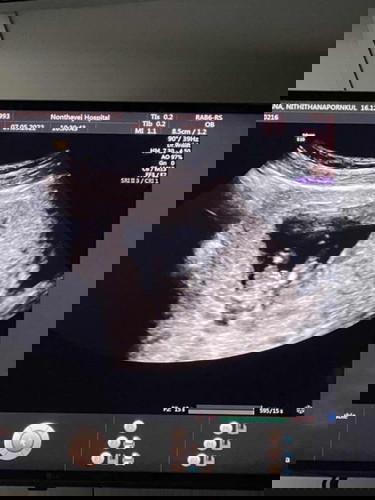

แม่ๆช่วยดูหน่อยค่ะ แบบนี้ผู้หญิงหรือผู้ชายคะ

อายุครรภ์ 13w อาจจะยังไม่ชัดเผื่อแม่ๆที่มีประสบการณ์จะช่วยดูได้บ้างค่ะ ขอบคุณค่ะ

น่าจะช.นะคะ ดีจังเลยร.พ.ให้ถ่ายรูปได้ด้วย ของเราห้ามยันทึกภาพ ให้มาเพียงรูปที่หมอแค๊ปให้ค่ะ

น่าจะชายนะคะ ของเราก็มีติ่งออกมานิดนึงตอน 12 วีคเหมือนกันค่ะ พอผล nift ออกก็เป็นผู้ชายจริงๆ ☺️

รุปที่สองเหมือนแหลมๆนะคะ🤣🤣

น่าจะผู้ชายนะคะ ตุยๆนูนๆ😂